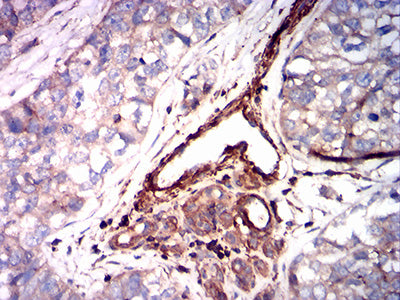

分类: 科研抗体货号: 31870别名: KOC; CT98; IMP3; KOC1; IMP-3; VICKZ3应用: WB,IHC,FCM反应种属: Human